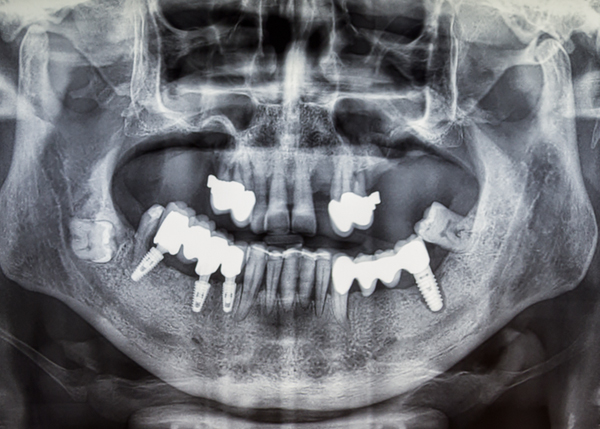

실패한 임플란트 재수술도 안전하게! -

임플란트 재수술은 첫 수술보다 더 까다롭고 난이도가 높은 수술인 만큼

의료진의 경험과 숙련도가 중요합니다.

다양한 임상 사례를 통해 축적된 노하우를 바탕으로

치주과 전문의 대표원장이 예측 가능하고 안정적인 재수술 결과를 제공합니다. - *치주과는 잇몸질환과 임플란트를 전문으로 치료하는 치과 내 전문분과